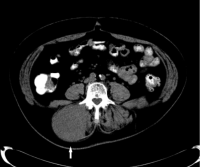

Image: Tap, et al. 2016. Lancet.